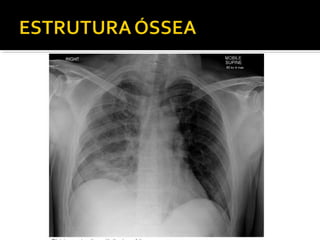

Este documento fornece parâmetros técnicos para realizar uma radiografia de tórax, incluindo posicionamento correto do paciente, dose adequada de radiação e estruturas anatômicas a serem avaliadas, como coração, pulmões, pleura, diafragma e ossos do tórax.